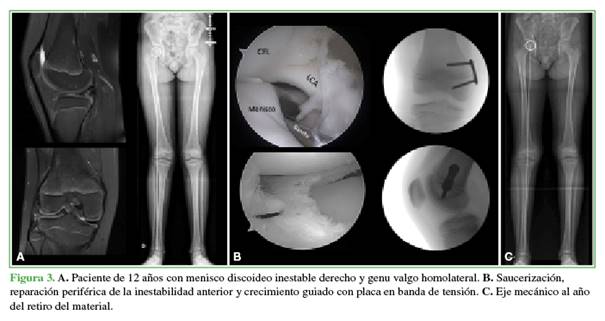

Luego del procedimiento artroscópico se continúa con el crecimiento guiado. Cuando estimamos que el crecimiento remanente será superior a 2 años, empleamos placas en banda de tensión,8 mientras que, si resta menos tiempo de crecimiento residual, utilizamos tornillos transfisarios (Figura 2).9

El eje mecánico se evalúa en consultas programadas cada 3 meses. Una vez que el eje está levemente sobrecorregido, zona -1 Stevens,11 se programa el retiro del material. Al año de este último procedimiento, se realiza una nueva telemetría para descartar el efecto rebote (pérdida de la corrección del eje con el crecimiento remanente del paciente) (Figura 3).